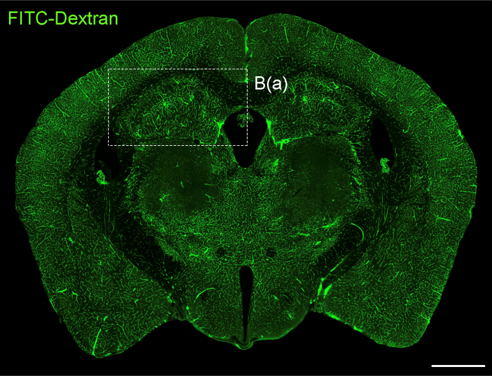

- 연구주제 : 뇌혈관장애-유래 인지기능 저하 및 근감소증 제어기전 연구

- 연구주제 : 뇌경색 동물모델 구축을 통한 뇌혈관 장애 및 염증제어 후보물질 발굴